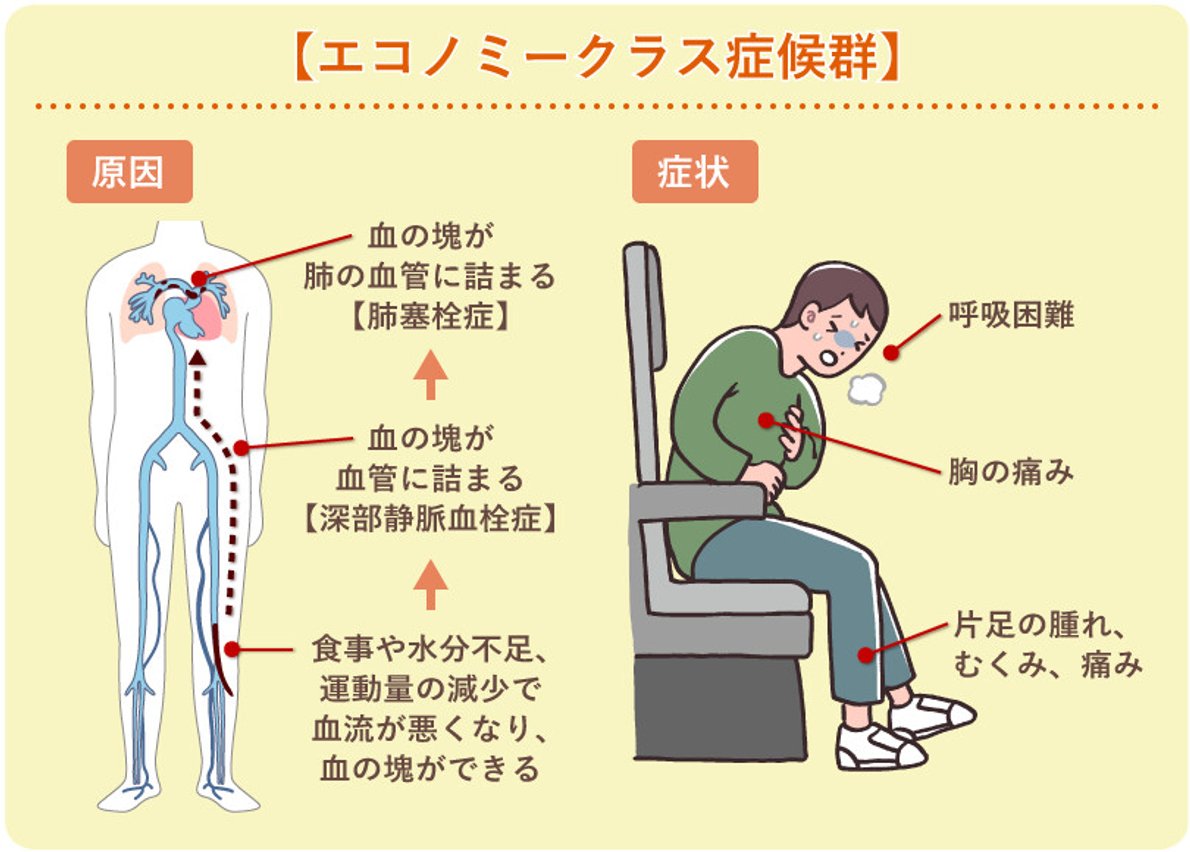

エコノミークラス症候群のイラスト素材29373435- PIXTA。

川崎 静脈血栓塞栓症浅田内科・循環器内エコノミークラス症候群。

エコノミークラス症候群広島の調剤薬局 FINE PLUS まえだ薬局・プラス薬局 のブログ。

4 エコノミークラス症候群 肺血栓塞栓症 に関するQ&A - 4 エコノミークラス症候群 肺血栓塞栓症 に関するQ&A -災害時の対応について一般社団法人日本呼吸器学会。

解剖生理学攻略ページ - この四コマ漫画を見ると ・エコノミー症候群 ・深部静脈血栓症 ・肺塞栓症Facebook。

エコノミークラス症候群病気と治療の検索サイト「メディカルブレイン」。

肺血栓塞栓症・エコノミークラス症候群 男性 のイラスト – フリーイラスト素材集 KuKuKeKe。

エコノミークラス症候群震災時に起こりやすい健康問題と予防法 1看護roo! カンゴルー。

4 エコノミークラス症候群 肺血栓塞栓症 に関するQ&A - 4 エコノミークラス症候群 肺血栓塞栓症 に関するQ&A -災害時の対応について一般社団法人日本呼吸器学会。

4 エコノミークラス症候群 肺血栓塞栓症 に関するQ&A - 4 エコノミークラス症候群 肺血栓塞栓症 に関するQ&A -災害時の対応について一般社団法人日本呼吸器学会。

エコノミークラス症候群 深部静脈血栓症 メカニズムのイラスト素材29374549- PIXTA。

エコノミークラス症候群:入院中に死亡8件 医療事故調査毎日新聞。